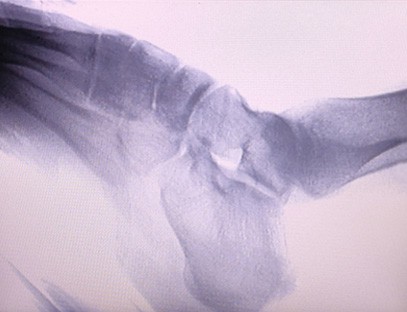

インスタントイメージングポータブルX線装置整形外科クリニック向けに特別に設計された、四肢のX線撮影を行う医療機器です。X線の透過性と人体のさまざまな組織間のX線吸収レベルの違いを利用して、内部構造情報を視覚画像に変換し、医師の診断と治療を支援します。特に、個人クリニック、獣医、ペット病院に適しています。四肢撮影X線装置は、ペット医療で使用され、獣医師の病気の診断と治療を支援します。

専門分野:整形外科クリニックのニーズに合わせて設計されており、特にX線画像手、手首、肘、肩、膝、足首などの手足。

鮮明な画像:高度なデジタル画像技術を使用して高品質のX線画像を提供し、医師が病状を正確に診断するのに役立ちます。